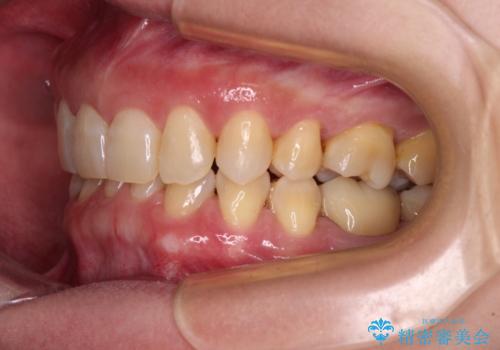

下顎2前歯の欠損 インビザラインによる抜歯矯正

- 下顎前歯欠損による歯列不正を気にして来院された患者様です。

下顎の歯列が小さく、下顎前歯が隠れてしまう過蓋咬合(ディープバイト)であったため、

マウスピースでの抜歯矯正特有の抜歯スペースに向かって奥歯が傾斜する動きが顕著に表れ、ディープバイトは改善されませんでした。

前歯のみが強く接触し、奥歯で咬めない期間も続いたため、ワイヤー装置などを補助的に使用し、何とか終了させることができました。